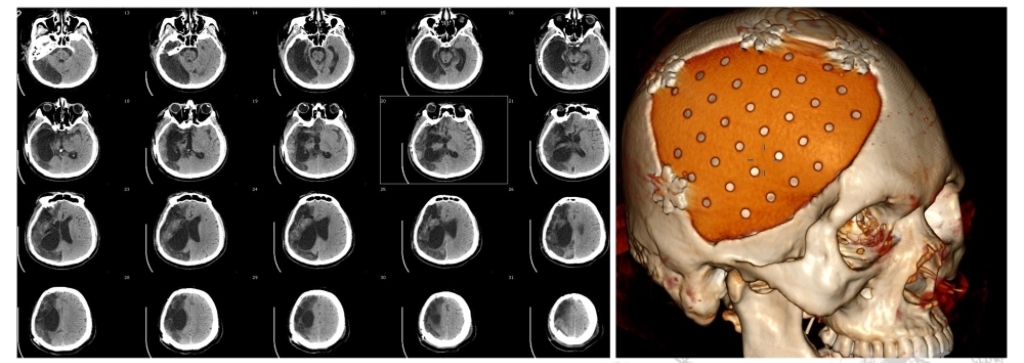

头颅CT清晰显示:右侧大脑半球大面积梗死显影,ASPECTS评分极低。按2017年指南,大核心坏死、大面积脑梗死已无取栓指征——常规路径下,这几乎是“放弃治疗”的信号。

尝试取栓,取栓后立即行去骨瓣减压术(术前当时联系了神经外科刁主任联合治疗——MDT复合手术)。